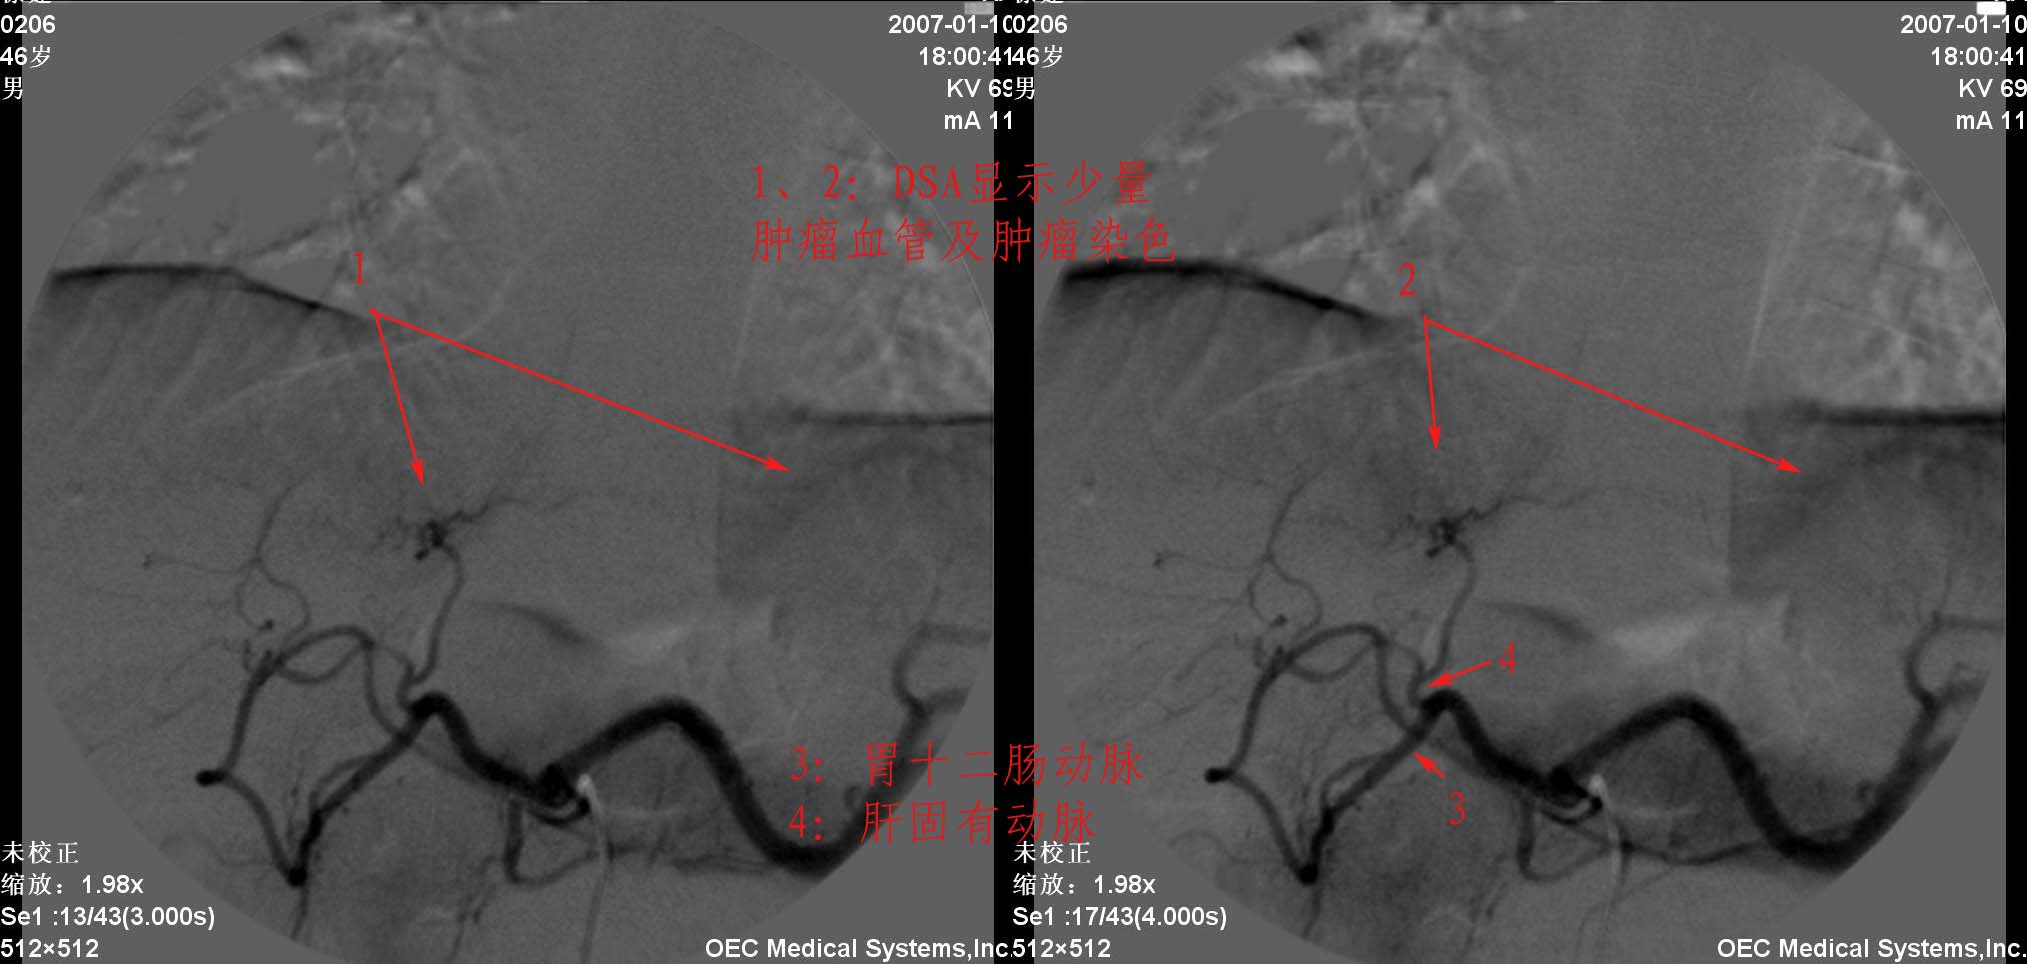

男性46岁,2005年5月份因原发性肝癌在上海中山医院手术,术后2个月即在手术周围新生肿瘤组织,在我院行介入治疗,治疗后5个月后随访在栓塞病灶的周围再次出现新病灶,患者再次奔赴中山医院手术,术后8个月复查afp升高,于我院先后两次介入治疗,06年11月mr复查未见复发病灶,07年复查即发现新病灶(见mr片),本次介入术中欲分别超选肝左和肝右动脉,但超选择左肝动脉失败,缘由是从肝固有动脉发出后突然转向左下方,同时轻度旋转,为确保疗效,故采取不得已的办法:栓塞胃十二指肠动脉.

介入过程:

一般术后病人或多次tae后再介入治疗比较麻烦,此病人造影见肝固有动脉明显变细,分支减少(术后改变),肝左动脉呈直角从肝固有动脉发出,给超选择带来困难.可通过两种方法试解决.第1种就是楼主采用的方法,用钢圈或明胶海绵进行栓塞治疗.第二种就是采用3fsp微导管超选择治疗.两种方法相比第一种更经济。

此病例采用了微导管,由于胃十二指肠动脉与肝左动脉相隔很近,肝内血管分支又很细小,故出现释放碘化油时返流明显,因而采取了胃十二指肠动脉栓塞.